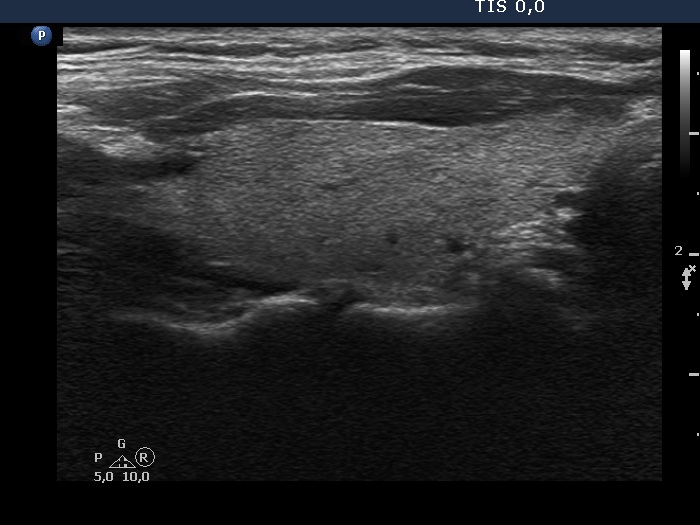

First examination (first row of images)

Clinical data: A 42-year-old woman requested a second opinion. She has been operated on for 3 months. A left lobectomy was performed, and histopathology disclosed a solitary, T2 papillary cancer. No further therapy was suggested.

Palpation: No abnormality.

Hormonal investigation indicated euthyroidism with TSH-level 2.56 mIU/L.

Ultrasonography. The right lobe was echonormal and intact. A hypoechoic, regenerative tissue was found in the isthmus and in the left thyroid bed. A small, deeply hypoechoic lesion was found in the middle of the left thyroid bed with the dimensions of 3x3x4 mm, width, depth and length, respectively.

Suggestion. I agreed with the suggestion of the surgeon. Yearly TSH and ultrasound was advised.